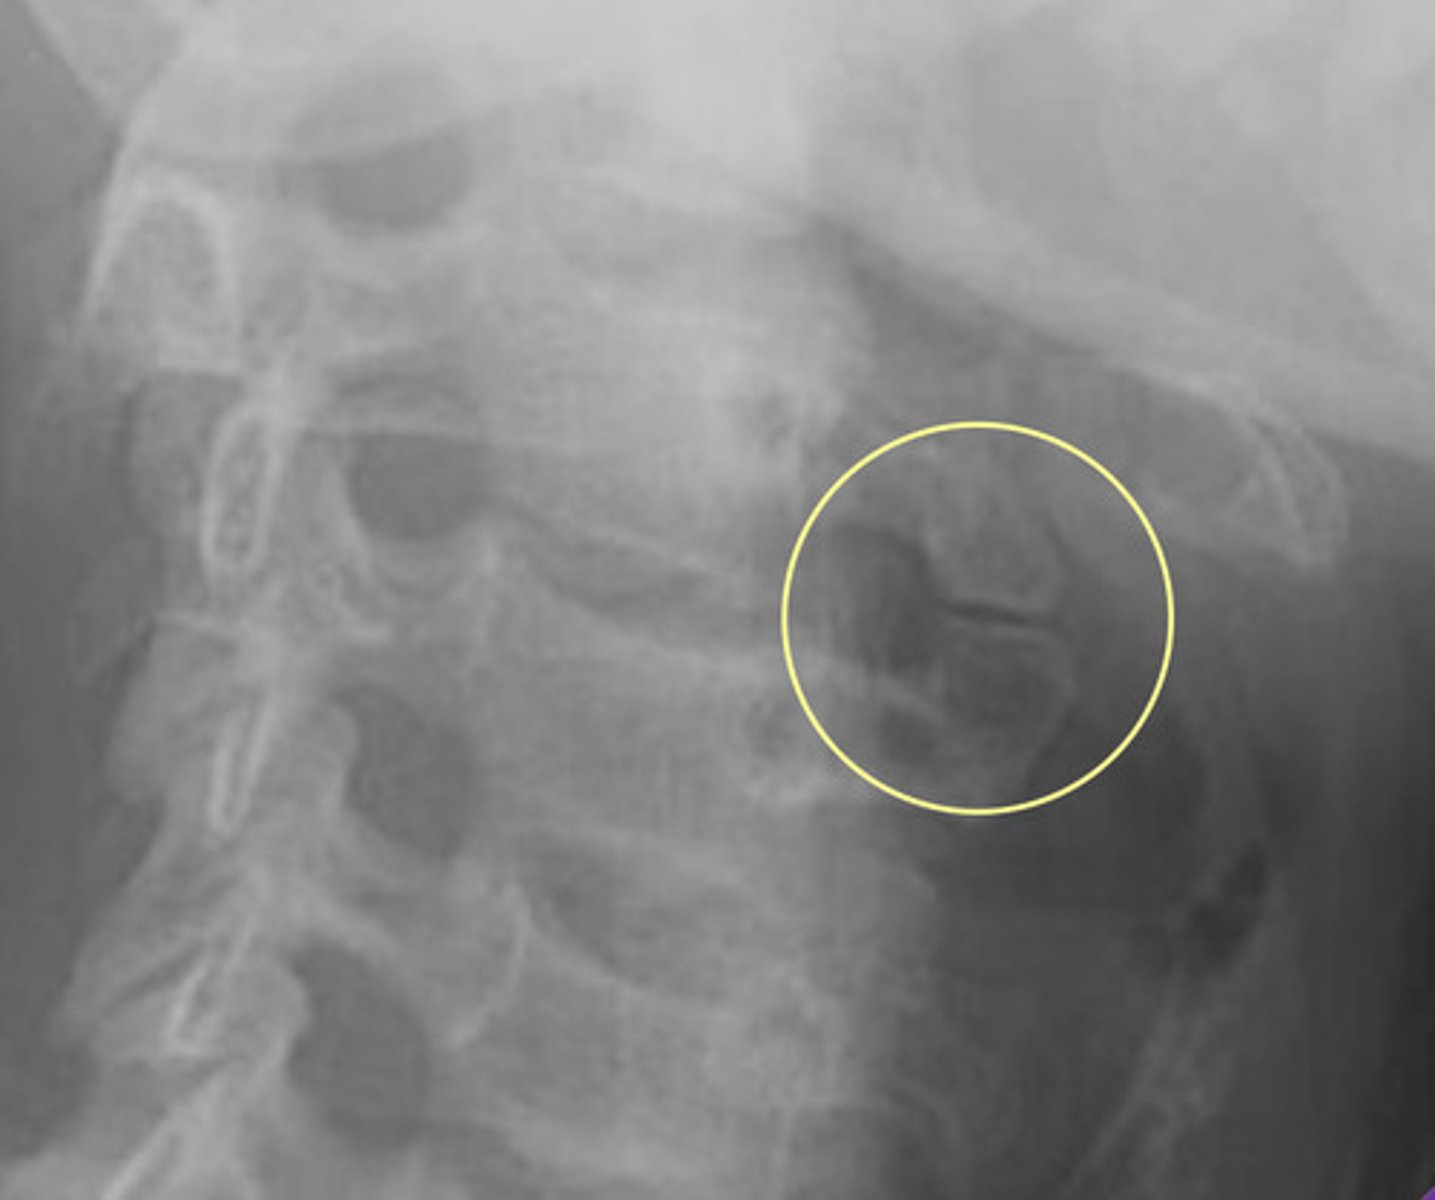

Imaging Findings of Incomplete Segmentation

— Hyperplastic transverse process ("batwing" appearance)

— Hypoplastic disc

— Possible accesory joint formation

— Occasional accessory joint degeneration

Image example of sacralization of L5